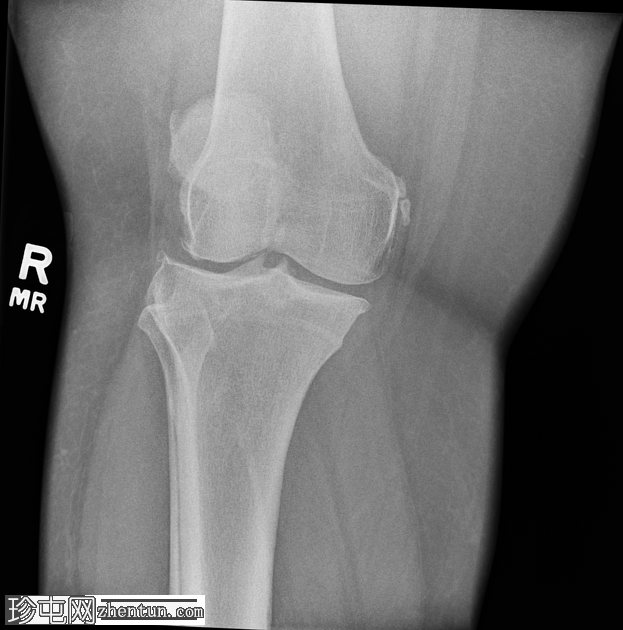

侧位片

右膝中度骨关节炎(3级),表现为内侧胫股关节和髌股关节间隙狭窄,边缘可见骨赘、髌骨骨刺和胫骨棘突。

内侧副韧带近端附着处股骨内侧髁附近可见长圆形软组织骨化,提示为佩莱格里尼-斯蒂达(Pellegrini-Stieda)损伤。